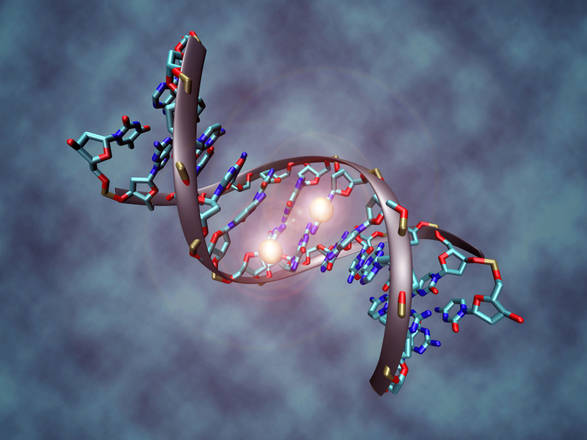

In uno studio pubblicato online in Genome Medicine il 26 agosto, i ricercatori sostengono di aver trovato cambiamenti diffusi e distintivi in un’ampia varietà di tumori, che coinvolgono i marchi chimici noti come gruppi metilici attaccati al DNA, che aiutano a governare i geni ( attivi o spenti) e infine, il comportamento della cellula. Questi marchi chimiche reversibili sul DNA sono conosciuti come epigenetica e insieme formano l’ epigenoma.

“Indipendentemente dal tipo di tumore solido, il modello di metilazione è molto diverso sui genomi di cellule cancerose rispetto alle cellule sane”, dice Andrew Feinberg, MD, MPH, professore di medicina, biologia molecolare, genetica e oncologia, e biostatistica presso la Scuola di Medicina Johns Hopkins University.

Per il loro studio, il team di ricerca ha preso campioni di DNA da tumori della mammella, del colon, del polmone, della tiroide e del pancreas e da tessuto sano e ha analizzato i modelli di metilazione sul DNA. ” Tutti i tumori avevano grandi blocchi di DNA in cui la metilazione è stata randomizzata con conseguente perdita di metilazione su grandi blocchi e guadagno di metilazione nelle regioni più piccole”, dice Winston Timp, Ph.D., un assistente professore di ingegneria biomedica presso la Johns Hopkins. “I cambiamenti nascono presto nello sviluppo del cancro, suggerendo che potrebbero cospirare con mutazioni genetiche, per favorire lo sviluppo del tumore”.

“Queste intuizioni sull’ epigenoma del cancro potrebbe fornire una base per lo sviluppo di screening precoce o trattamento preventivo della malattia” , dice Timp, suggerendo che la metilazione differenziata lascia un’ “impronta digitale” che potrebbe potenzialmente essere usata per distinguere i tumori in fase iniziale dalle escrescenze innocue. ” Ancora meglio”, dice il ricercatore, ” sarebbe trovare un modo per impedire il diffondersi dell’ una impronta digitale cancerosa”.